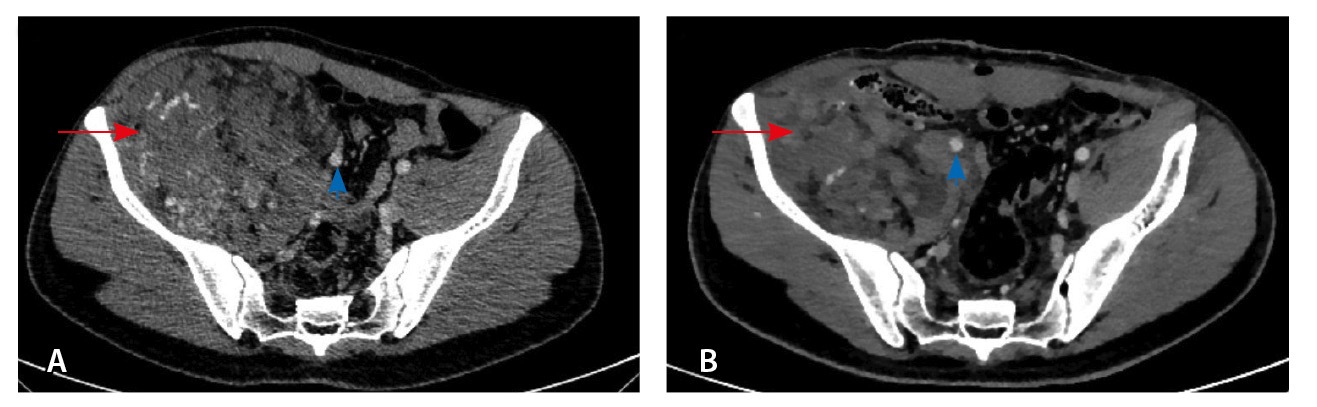

Результаты дооперационной мультиспиральной компьютерной томографии органов брюшной полости и забрюшинного пространства (рис. 1, 2): «В забрюшинном пространстве справа визуализируется образование, исходящее из подвздошно-поясничной мышцы, с выходом вдоль сосудистого пучка на верхнюю треть бедра. Образование с четкими и ровными контурами, размерами 145 × 125 × 125 мм. Структура образования гетерогенная, плотность в нативную фазу исследования от –40 до 50 HU, содержит единичные кальцинаты, жировую ткань и мягкотканный компонент. На фоне контрастирования в артериальную и венозную фазы в структуре выявляются извитой формы участки гиперконтрастирования (сосудистая сеть). Максимальное накопление контрастного препарата происходит преимущественно к отсроченной фазе исследования. Усредненные плотностные характеристики составляют 25, 36, 53 и 59 HU в нативную, артериальную, венозную и отсроченную фазы соответственно. Опухоль оттесняет тазовую брюшину, правую подвздошно-поясничную мышцу, илеоцекальный угол кпереди. Образование тесно прилежит сзади к крылу правой подвздошной кости и лобковой кости, спереди – к прямой и внутренней косым мышцам живота, верхним контуром – к поясничной мышце. Медиально в средней трети по контуру образования проходят правые наружные и внутренние подвздошные сосуды, со сдавлением наружной подвздошной вены. Данных за распространение на прилежащие внутренние органы и клетчатку не получено. Кости без деструктивных изменений».

Рис. 1. Мультиспиральная компьютерная томография органов брюшной полости и забрюшинного пространства с болюсным внутривенным контрастированием: А – нативная фаза, Б – артериальная фаза, В – венозная фаза, Г – отсроченная фаза. Крупное гетерогенной структуры образование забрюшинного пространства справа, с фокусами гиперваскуляризации в структуре. Тесно прилежит к крылу подвздошной кости и подвздошным сосудам, оттесняя последние медиально

При контрольной томографии, проведенной на 5-е сутки после операции, забрюшинно справа определялась остаточная ткань опухоли размерами 125 × 81 × 90 мм. Резидуальный фрагмент прилегал к правой подвздошной кости, по ходу подвздошных сосудов, с распространением на переднюю поверхность правого бедра. Признаков экстравазации контрастного препарата не обнаружено (рис. 3).

Рис. 3. Мультиспиральная компьютерная томография органов брюшной полости и забрюшинного пространства с болюсным внутривенным контрастированием, венозная фаза. А – исследование до операции, Б – исследование после операции: резидуальный фрагмент образования (красная стрелка) тесно прилежит к подвздошной кости и подвздошным сосудам (головка синей стрелки)